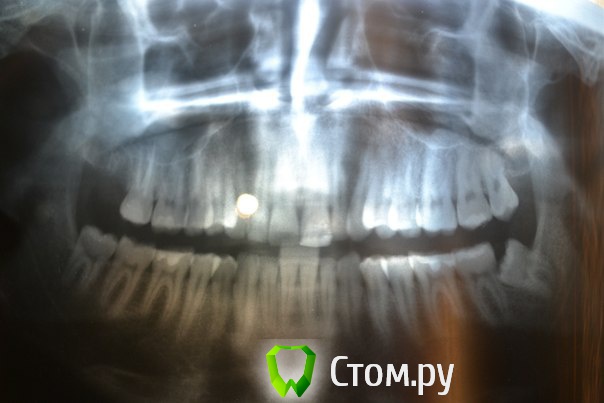

Доброго времени суток,помогите пожалуйстабеспокоит заложенность носа уже 3ий год,обший ослабленный иммунитет что выражается в частых простудах,возраст 25 лет,причина этого гдето в зубах,так как кроме этого проблем небыло никогда,когда начились эти проблему начал ходить к стомалогам мне сделали порядка 7 пломб,в одном был пульпит,как пульпит переличили стало легче но не до конца ,затем на мскт увидели кисту под депульпированной 7кой,

вот зуб пролечил у ильи мера,в 2 этапа,первый раз он сделал,и залили лекарство и сказал зуб врядли сохраним,через месяц второй прием все доделал и сказал что все хорошо,после этого общее состояние стало хуже,возможно из-за того что врач сказал что все с пульпы сливалось прямо в пазуху, вот это делали в марте ,после этого сделал мскт киста с зуба увеличилась с 1см до 1,5см, я лег в больничку местную и мнее ее вырезали,после этого прошел 1 месяц улучшений нет все также заложенность в носе и пониженный иммунитет,не подскажите что делать?кисту просто вырезали резекцую корня зуба не делали вот снимки до вырезания кисты после первого раза лечения каналов